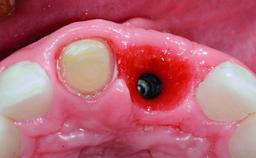

Replacement of an Upper Right Central Incisor with Root Resorption: Ridge Preservation, Delayed Placement of an NC Bone Level Roxolid Implant

A 32-year-old female Caucasian patient with a compromised maxillary right central incisor was referred to us by a general dentist. Her chief complaints were discomfort and mobility of tooth 11 with unsatisfactory esthetics due to discoloration. The patient reported a previous trauma, some years earlier, as the origin of pathology on the afflicted tooth. Anamnesis was negative for any other dental or periodontal pathology in the remaining dentition. The patient did not take any medication and reported to be a light smoker (5–10 cigs/day). She had high esthetic expectations of her treatment. The extraoral examination revealed a high smile line with full exposure of her maxillary teeth and surrounding soft tissue in the area between the second premolars.

Type of Implants Reduced-Diameter|Two-Piece